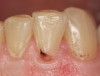

Figure 1  A Class V carious lesion on a lateral incisor.

Figure 1

When compared with earlier composites, modern composites shrink less and wear less. In addition, they have more resistance to water and chemical breakdown, better mechanical strength, highly polishability, and better color stability and matching, and are available in various consistencies from flowable to packable.9,10 Composite resins have been combined with other materials to improve caries resistance, as seen with resin ionomers.3 Advancements in bonding technologies, especially the eight generations of dentin bonding, have improved the longevity of restorations and reduced postoperative sensitivity. Resin bonding agents produce an oxygen-inhibited outer layer that remains uncured, therefore the addition of composite materials joins to it.11 Case 1 shows results of modern bonded composites restoring a Class V cavity with no mechanical retention (Figure 1 through Figure 3).